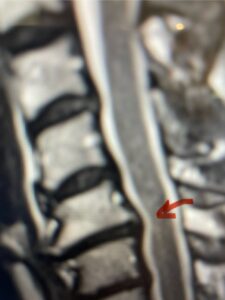

In this next case, this patient is a 47 year-old female who presents with intractable low back pain with severe pain, numbness, and weakness in the right lower extremity that had gotten progressively worse over a year. The patient had failed conservative management including physical therapy and epidurals. She was noted to have ⅘ weakness of plantar flexion. MRI demonstrated a large right L5-S1 disc herniation with severe compression of the descending right S1 nerve root (Fig 3). It was decided to perform a right L5-S1 hemilaminectomy for removal of the disc fragment and decompress the S1 nerve root. When you expose the disc, one must be certain to release any anterior adhesions to the nerve root in order to prevent a dural tear during retraction of the nerve root. It is also important to make sure during exposure and you finally encounter the dura after removing the ligamentum and fat, to make sure you are looking at the nerve root and not the main trunk of the thecal sac because if you don’t you can avulse or damage the nerve root if you retract the wrong structure.

Fig. 3a: Sagittal and axial T2-weighted lumbar MRI images demonstrating large right L5-S1 disc herniation (red arrows)